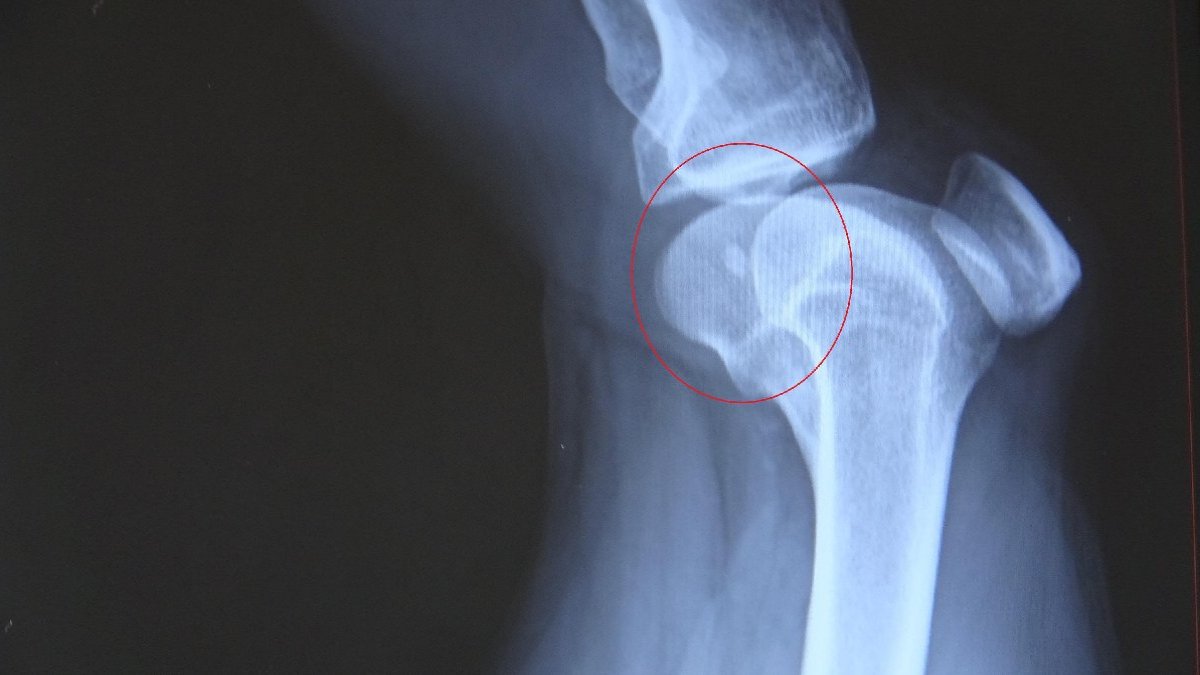

Çağlar, sağ bacağının diz kısmına mermi isabet ettiğini fark etti. Yakınları tarafından Karadeniz Teknik Üniversitesi (KTÜ) Tıp Fakültesi Farabi Hastanesine götürülen Çağlar, tedavi altına alındı. Çağlar'ın diz kapağındaki mermi ameliyatla çıkartıldı. Mermi balistik incelemeye alınırken, jandarma ekipleri silahı ateşleyen kişiyi tespit etmek için çalışma başlattı.